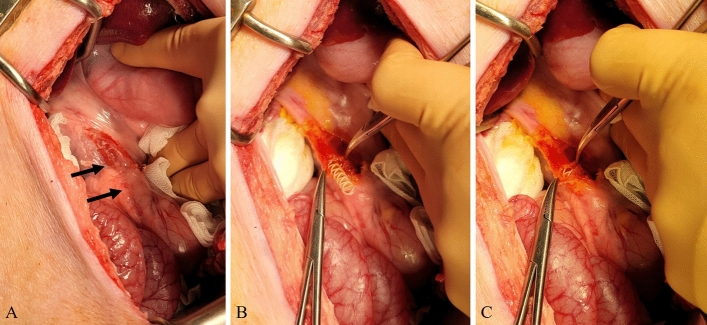

All surgical procedures were performed by two experienced hepatobiliary surgeons (Y.C. and E.S.H.). Anesthesia was induced using intramuscular injection of tiletamine-zolazepam (2 mg/kg; Zoletil 50, Virbac S.A., Carros, France) and xylazine (2 mg/kg; Rompun, Bayer HealthCare, Leverkusen, Germany). Thereafter, endotracheal intubation was performed by a veterinarian and general anesthesia was achieved using 1.5–2% isoflurane and oxygen. After thorough shaving and skin preparation, a sterile drape was applied to the area. A midline upper laparotomy was performed and the CBD was identified and exposed. The CBD was opened transversely (Fig. 3). In the control group, the CBD incision was closed with interrupted sutures using monofilaments (polydioxanone, PDS II 5-0, Ethicone, Somerville, NJ, USA). In the stent group, a 4-mm or 6-mm biodegradable biliary stent was inserted into the CBD according to the bile duct diameter (Fig. 3). When the CBD length was less than 6 cm, the stent was cut with scissors to fit the CBD. CBD incision-site closure was performed in the same manner as in the control group. The laparotomy was closed with multifilament and monofilament sutures in the peritoneum, fascia, and subcutaneous layers (polyglactin, Vicryl 0, Ethicone, Somerville, NJ, USA), and skin (nylon, Ethilon 3-0, Ethicone, Somerville, NJ, USA).